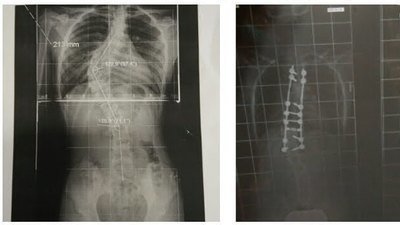

Tengo una hija operada de escoliosis desde hace 2 años, y anteriormente estuvo otros 3 años llevando corsé ortopédico. Durante todo este tiempo, he pedido al colegio y ahora al instituto que los libros que tuviera que usar para el curso correspondiente, se pudieran encontrar en formato trimestral, para evitar incrementar el peso en su espalda (por prescripción médica no puede llevar más del 10% de su peso corporal); pero año tras año, me encuentro con que los libros que le piden, no los hay en formato trimestral, con lo que me veo obligada a adquirirlos (no puedo optar al préstamo del ANPA) y romperlos por temas, para que la niña lleve a clase únicamente las hojas que corresponden al tema que está dando.

Pido que se requiera a los colegios y a los institutos a utilizar libros trimestrales en todos los cursos. Mi hija cursará este año 1º de Bachiller y llevamos 5 años fraccionando los libros en temas, con el desperdicio que supone (ese libro no lo podrá utilizar otro alumno) y el coste añadido (no podemos optar al préstamo de libros). Gracias.